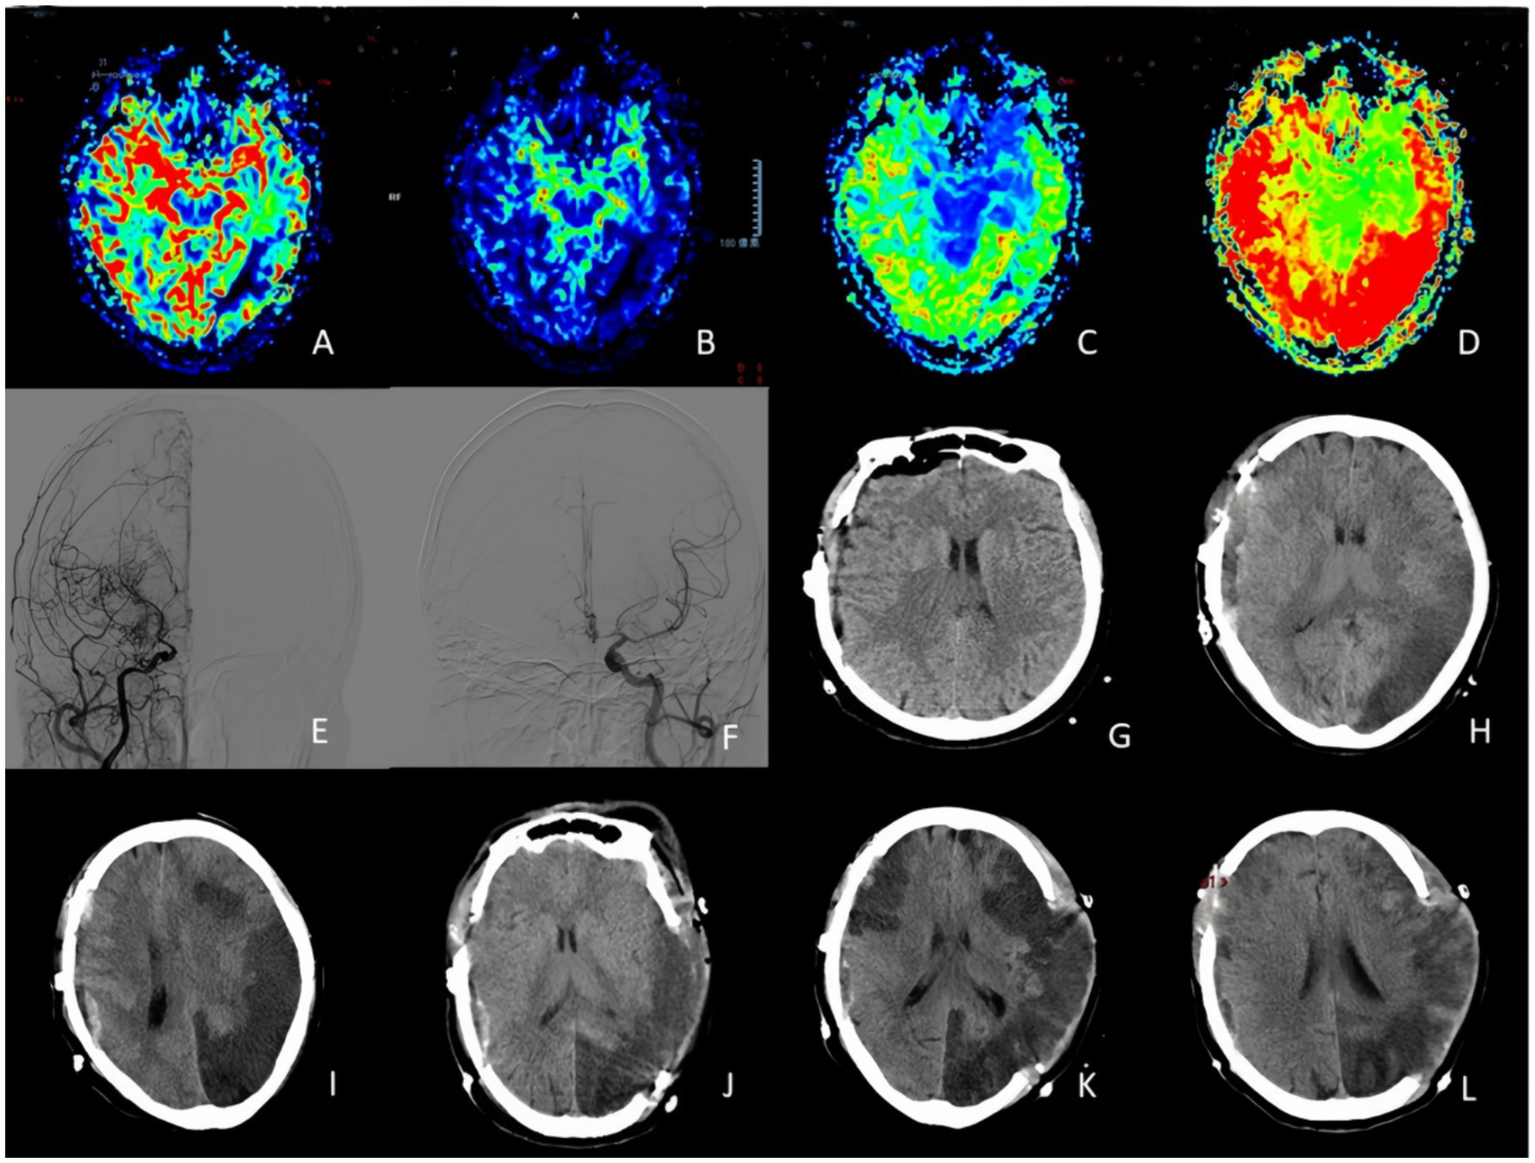

We defined uMMD as the presence in DSA of ipsilateral ICA or MCA occlusion together with the development of moyamoya vessels and the presence of progressive stenosis on the contralateral ICA or MCA without the evidence of moyamoya vessels, cerebral perfusion studies reveal a similar or even more severe reduction in perfusion on the occluded side compared to the stenotic side (Figure 1) clinical symptoms in these patients are typically attributed to ischemia caused by the stenotic side.

Figure 1

Unstable moyamoya disease. (A) Middle cerebral artery occluded and presence of moyamoya vessels. (B) Middle cerebral artery stenosis. (C–F) PWI show MTT, TTP, CBF, and CBV indicated bilateral ischemia, with the degree of ischemia being less pronounced on the left stenotic side compared to the right occluded side. PWI, perfusion-weighted imaging; CBV, cerebral blood volume; CBF, cerebral blood flow; DSA, digital subtraction angiography; MTT, mean transit time.